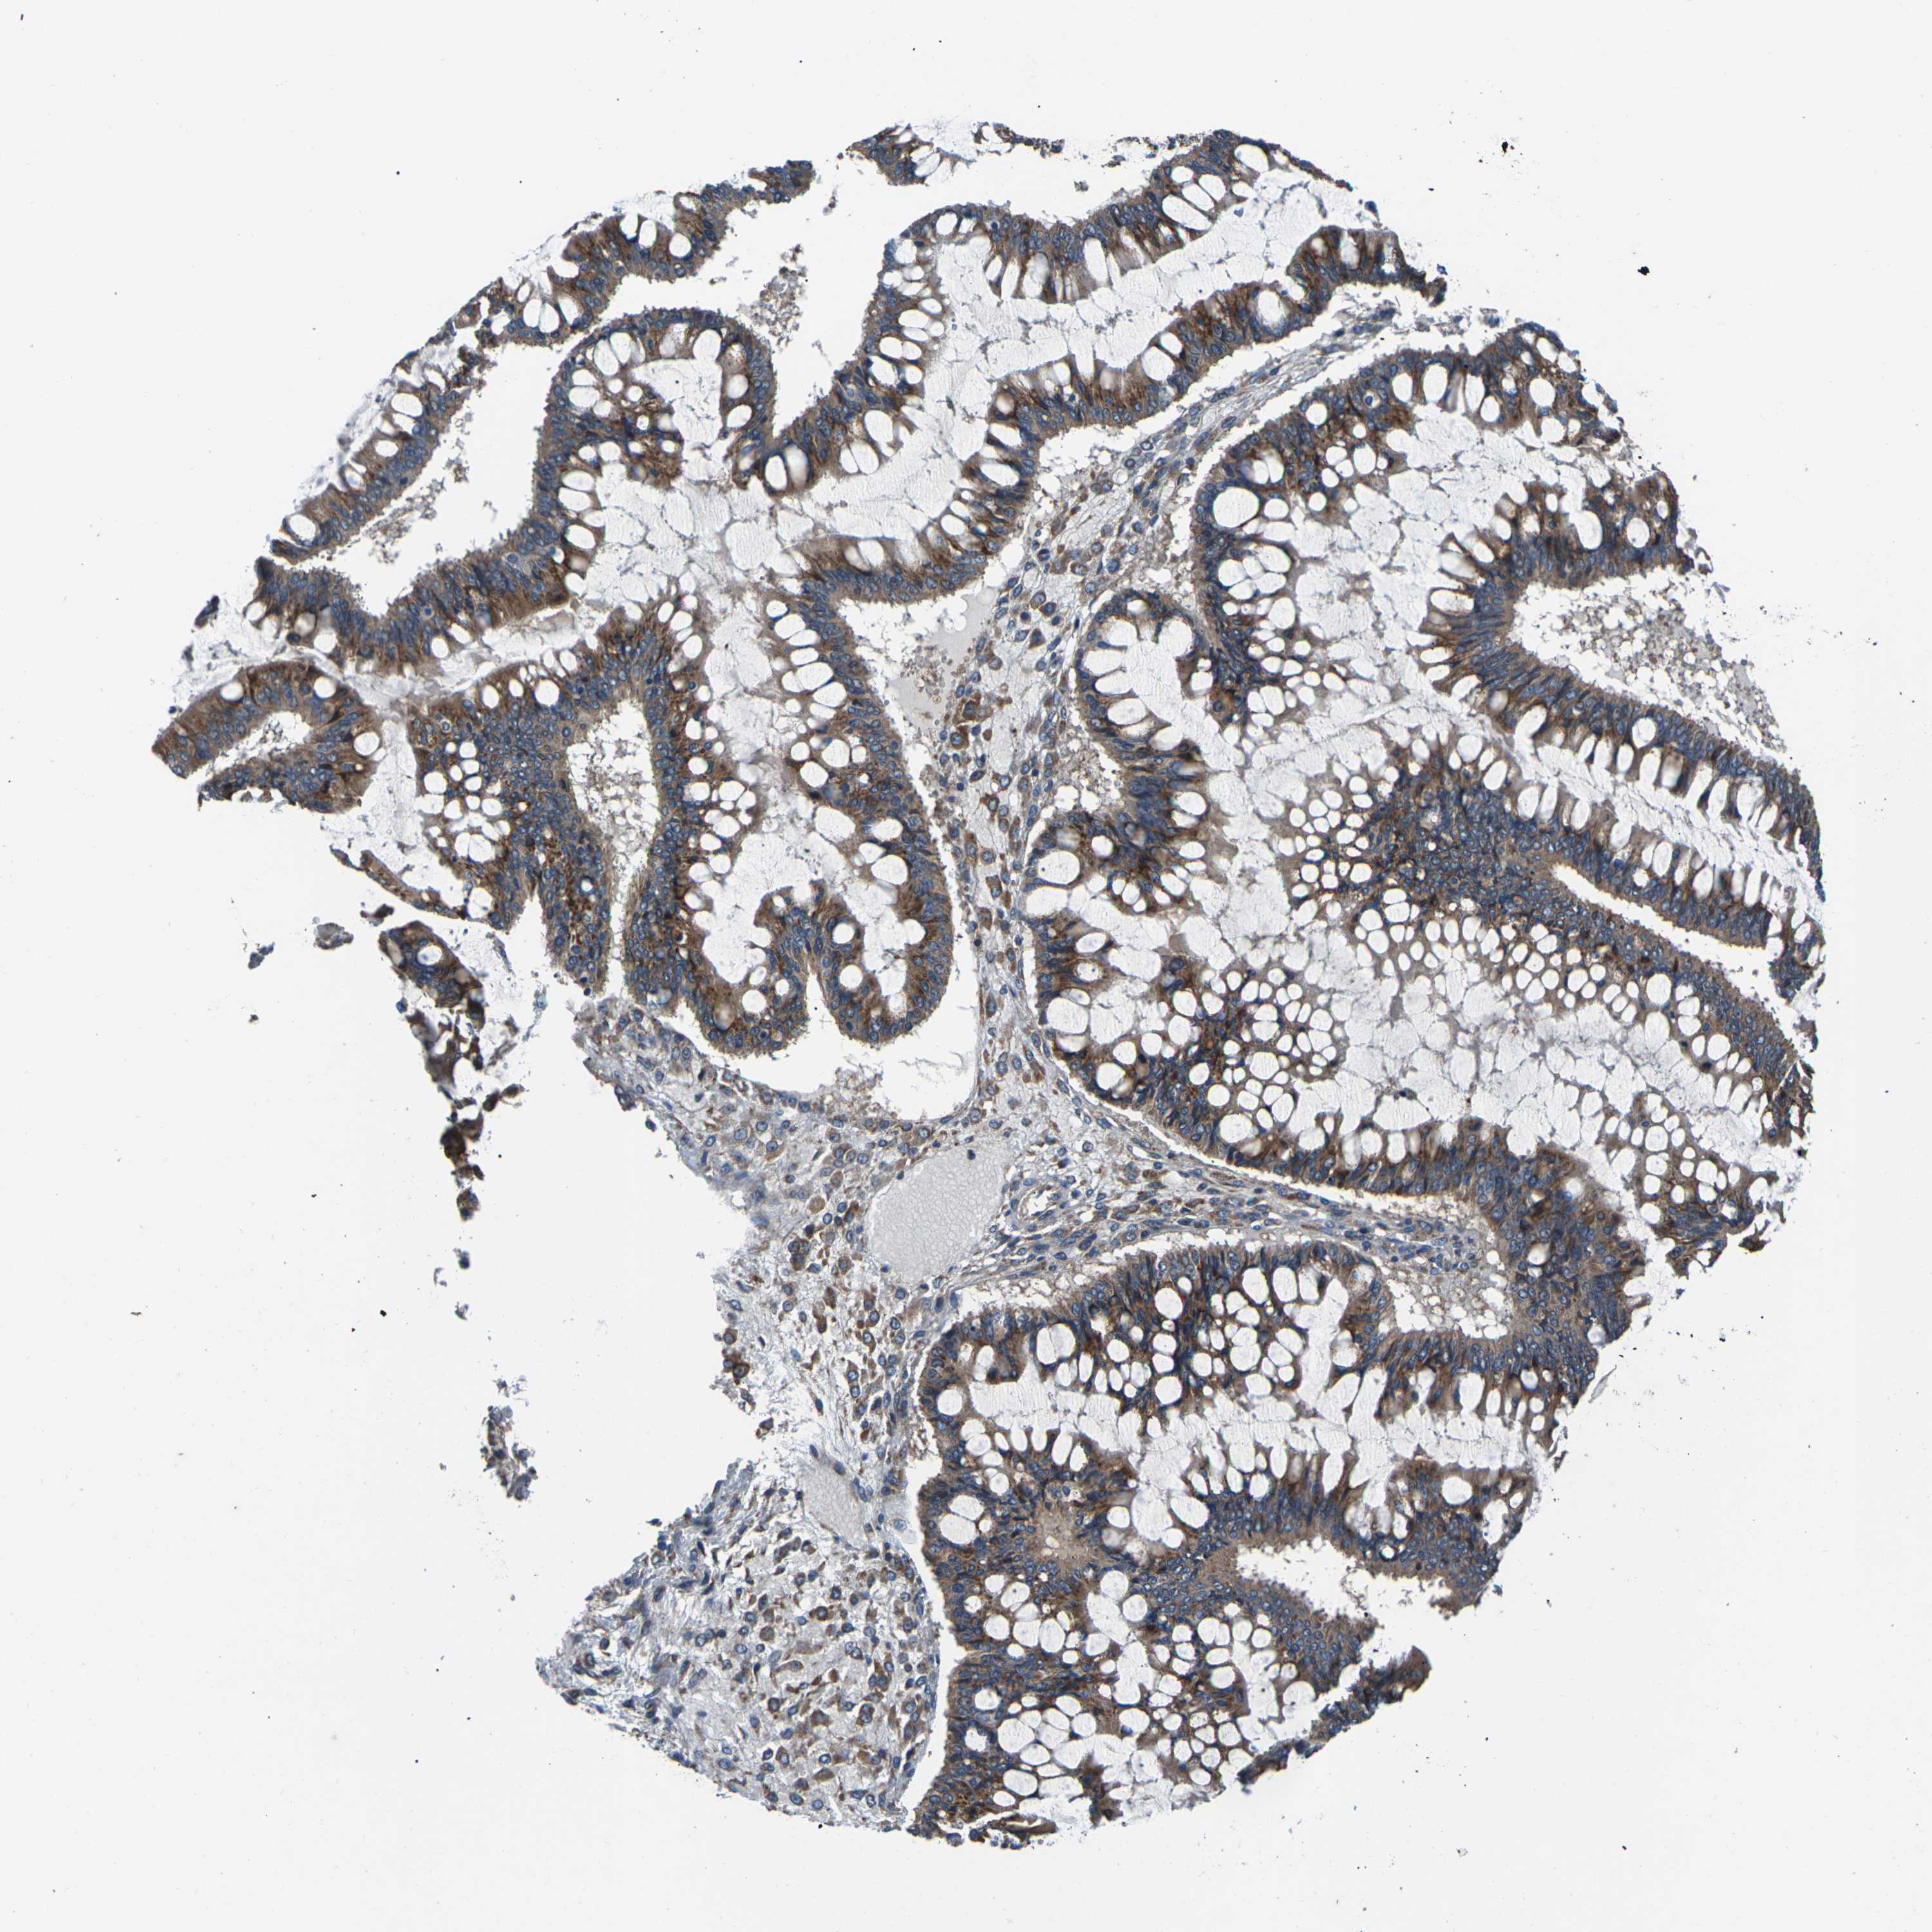

OVARIAN CANCER - Protein expressioni

A mouse-over function shows sample information and annotation data. Click on an image to view it in a full screen mode. Samples can be filtered based on level of antibody staining by selecting one or several of the following categories: high, medium, low and not detected. The assay and annotation is described here.

Note that samples used for immunohistochemistry by the Human Protein Atlas do not correspond to samples in the TCGA dataset.

Antibody stainingi

Antibody staining in the annotated cell types in the current human tissue is reported as not detected, low, medium, or high, based on conventional immunohistochemistry profiling in selected tissues. This score is based on the combination of the staining intensity and fraction of stained cells.

Each image is clickable and will lead to virtual microscopy that enables deeper exploration of all samples and also displays staining intensity scores, fraction scores and subcellular localization as well as patient and tissue information for each sample.

Antibody CAB014883

Staining

High

Medium

Low

Not detected

Intensity

Strong

Moderate

Weak

Negative

Quantity

>75%

75%-25%

<25%

None

Location

Nuclear

Cytoplasmic/membranous

Cytoplasmic/membranous,nuclear

Cystadenocarcinoma, serous, NOS

Carcinoma, endometroid

Cystadenocarcinoma, mucinous, NOS

Carcinoma, NOS